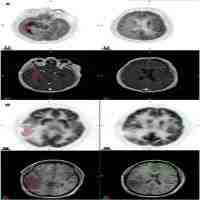

| Abstract | BACKGROUND: Aim of this prospective longitudinal study was to identify static and dynamic O-(2-[18F]fluorethyl)-L-tyrosine PET (18FET-PET) derived imaging biomarkers in glioblastoma (GB) patients to obtain additional information concerning prognosis and monitoring of therapy. METHODS: 79 patients with newly diagnosed GB were included; 42 patients underwent stereotactic biopsy (unresectable tumors) and 37 patients microsurgical tumor resection. All patients were scheduled to receive radiotherapy plus concomitant and adjuvant temozolomide (RCx/TMZ). 18FET-PET evaluation using static and dynamic parameters was done prior to biopsy/resection, after resection, 4-6 weeks following RCx and after three cycles of TMZ. Endpoints were survival and progression-free-survival. Prognostic factors were obtained from proportional hazards models. RESULTS: Biological tumor volume before RCx (BTVpreRCx) was the most important 18FET-PET derived imaging biomarker and was independent of MGMT promoter methylation and clinical prognostic factors: patients with smaller BTVpreRCx had significant longer progression free (PFS) and overall survival (OS). 18FET time activity curves (TAC) before treatment and their changes after RCx were also related to outcome: patients with initially increasing TAC and those exhibiting a switch from decreasing to increasing TAC after RCx experienced longer progression-free-survival. CONCLUSIONS: BTVpreRCx and TAC represent important 18FET-PET-derived imaging biomarkers in GB. Increasing TAC are associated with prolonged PFS. The BTVpreRCx is a strong prognostic factor for PFS and OS independent of the mode of surgery. Our data furthermore suggest that patients harbouring resectable GB might benefit from maximal PET-guided tumor resection. SECONDARY CATEGORY: Clinical Neuro-Oncology. |